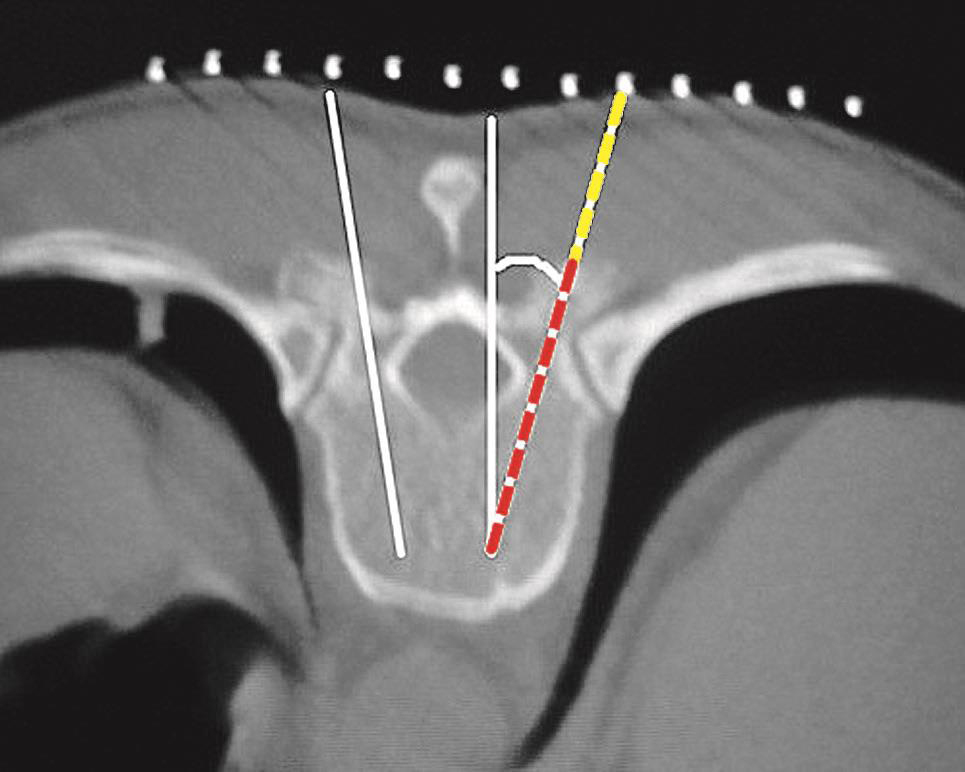

一般的CT机架可以调整角度(图3-3-8),调整机架角度进行扫描是寻找操作平面的关键举措,不同的穿刺途径和手术目的要求机架调整的角度也不同,如L 4/5 经椎间隙侧方入路时,如果手术平面无髂骨阻挡,则采用零度扫描(见图3-3-6A、图3-3-8B),否则为了避开髂骨阻挡,机架应向头侧倾斜(图3-3-6B、图3-3-8C);用于射频靶点消融或内镜髓核摘除的椎板间入路,如果扫描角度与椎间隙平行,将多有椎板阻挡(图3-3-9),其要点在于穿刺靶点为直接突出的椎间盘,而穿刺途径又必须避开椎板经过椎板间隙才能成功,因此要求调整到既能显示靶点又经过椎板间隙的角度,一般向足侧倾斜(图3-3-8A、图3-3-10);椎弓根入路则沿椎弓根轴线扫描(图3-3-11)。

图3-3-9 机架平行椎间隙扫描

A.沿椎间隙轴线扫描(红坐标线);B.横断位层面多有椎板阻挡

图3-3-10 适当角度扫描

A.经过椎板间隙的角度扫描(红坐标线);B.寻找出符合手术要求的操作平面